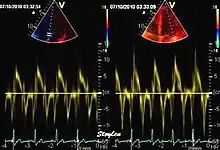

Like Doppler flow, tissue Doppler can be acquired both by spectral analysis (spectral density estimation) as pulsed Doppler[1] and by the autocorrelation technique as colour tissue Doppler[2] (duplex ultrasonography). While pulsed Doppler only acquires the velocity at one point at a time, colour Doppler can acquire simultaneous pixel velocity values across the whole imaging field. Pulsed Doppler on the other hand, is more robust against noise, as peak values are measured on top of the spectrum, and are unaffected of the presence of clutter (stationary reverberation noise).

This has become a major echocardiographic tool for assessment of both systolic and diastolic ventricular function. However, as this is a spectral technique, it is important to realise that measurement of peak values is dependent on the width of the spectrum, which again is a function of gain setting.

The method measures annular velocities to and from the probe during the heart cycle.

Annular velocities summarize the longitudinal contraction of the ventricle during systole, and elongation during diastole. Peak velocities are commonly used.